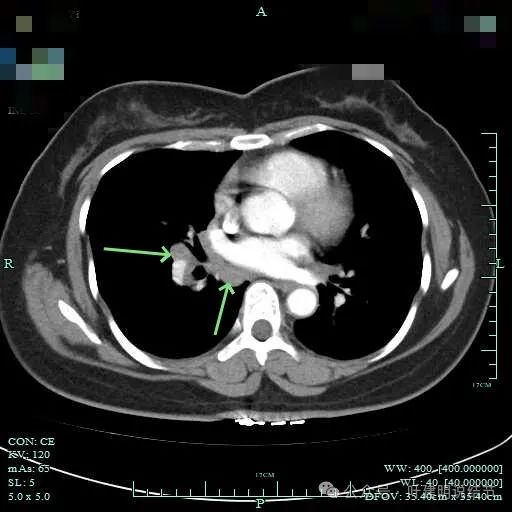

病灶纵隔窗上是软组织影,表面不平,形态不规则。上腔静脉旁有肿大淋巴结。

病灶膨胀性不明显。

邻近支气管有扩张,表面不平,分叶明显。

病灶有毛刺与小棘突征,有邻近细支气管扩张,表面不平,膨胀性不明显。

毛刺征明显,灶边细支气管扩张。

病灶整体轮廓还是较为清楚的。